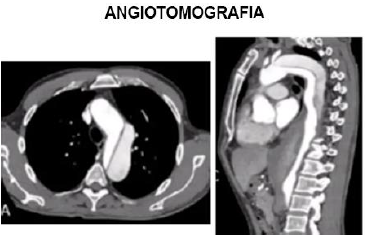

Paciente, homem, 66 anos, comparece a consulta ambulatorial assintomático. Refere ser tabagista pesado. Refere que há 3 meses teve quadro de dor torácica importante, referida como pior dor da vida com irradiação para as costas. Foi ao Pronto Socorro, sendo realizado Eletrocardiograma e marcadores de necrose miocárdica que estavam normais e então recebeu alta. No exame físico, paciente não apresenta alterações. Pela suspeita diagnóstica de etiologia da dor torácica que aconteceu há 3 meses, foi solicitado o exame abaixo e o paciente traz no retorno em 1 mês, mantendo-se assintomático:

Analise as afirmativas abaixo:

I. O paciente provavelmente apresentou dissecção aguda de aorta na sua ida ao Pronto Socorro há 3 meses. Pelo achado da imagem, pode-se concluir que se trata de Dissecção de Aorta Stanford A.

II. Nos casos de dissecção crônica (caso do paciente), deve-se avaliar outros parâmetros para indicação cirúrgica, como tamanho de aneurisma de aorta, se dor refratária, Insuficiência aórtica associada.

III. Caso na ida ao Pronto Socorro tivesse sido realizada a tomografia e identificado o diagnóstico, o paciente tinha indicação cirúrgica de urgência/emergência.

IV. Deve-se prescrever medicações para manter o controle do duplo produto, ou seja, manter Pressão arterial bem controlada e frequência cardíaca próximo a 60 batimentos por minuto.

Assinale a alternativa correta.